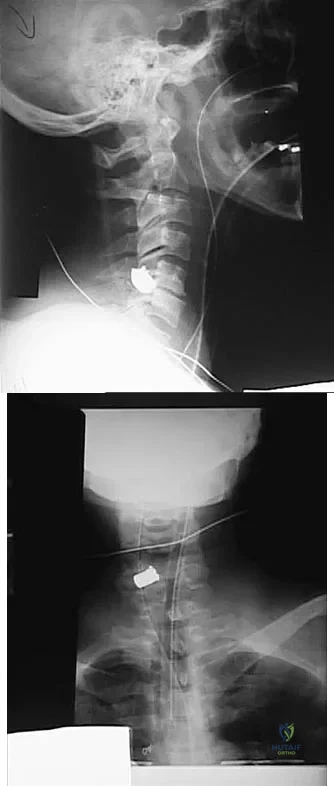

Figures 20a and 20b show lateral and AP radiographs of a 49-year-old man who sustained a gunshot wound through the left shoulder. He reports neck pain and examination reveals weakness in all four extremities. What is the priority of evaluation?